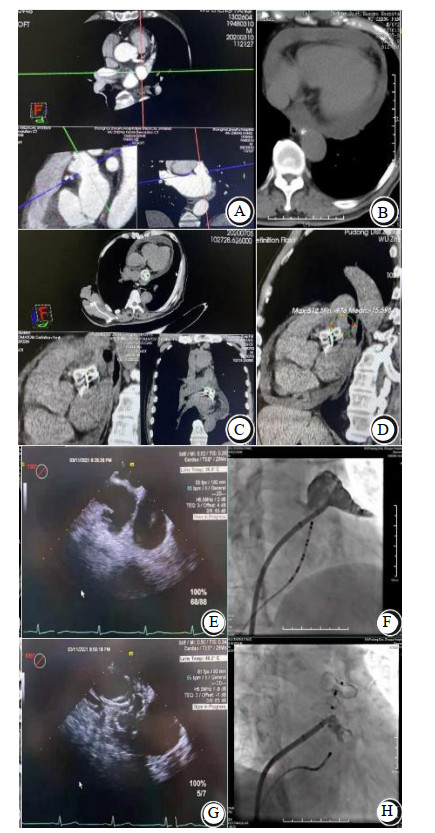

本组病例LAAC后心脏压塞发生率,Watchman为0.71%(4/562例),LAmbre为0.93%(2/216例),LACbes为6.6%(6/91例),Laager为6.25%(1/16例);同期文献报道LAmbre心脏压塞发生率2.2%(5/224例)[9]。平均左心房直径(43.2± 5.3)mm,6例LAAC联合冷冻消融手术;左心耳菜花型8例,鸡翅型5例;左心耳/ 肺动脉位置B型11例,A型1例(病例13),C型1例(病例8);B型患者D10为(2.15± 1.5)mm,D15为(1.71± 1.5)mm,minD_深度(10± 2.6)mm;盘式封堵器密封盘平均直径(29.5± 2.8)mm;心脏压塞恢复后复查CTA患者10例,封堵器展开完全,8例锚钩贴靠肺动脉,病例8为鸡翅型左心耳,左心耳肺动脉位置C型,封堵器锚钩贴靠左上肺静脉;病例13为鸡翅型左心耳,左心耳肺动脉位置A型,封堵器锚钩贴靠左上肺静脉,见表 2。本研究汇总同期LAAC后左心房CTA复查病例,封堵器锚钩贴近肺动脉及左上肺静脉发生率为20%。代表性LAAC病例2,12,见图 1和图 2。

| 患者(病例12)心脏CTA检查(A:左心耳近鸡翅反折处与肺动脉主干近段毗邻密切;B:术后3个月复查TEE正常,术后4个月急性心脏压塞,中-大量心包积液;C、D:左心耳置入2 834 mm LACbes,贴靠肺动脉,锚钩更加贴近左上肺静脉);TEE检查(E:LACbes封堵前;G:LACbes封堵后);DSA检查(F:左心耳造影为鸡翅型;H:置入LACbes后) 图 2 左心耳置入LACbes封堵器后4个月发生延迟性心脏压塞 Fig 2 Delayed cardiac tamponade occurred 4 months after LAAC with LACbes |